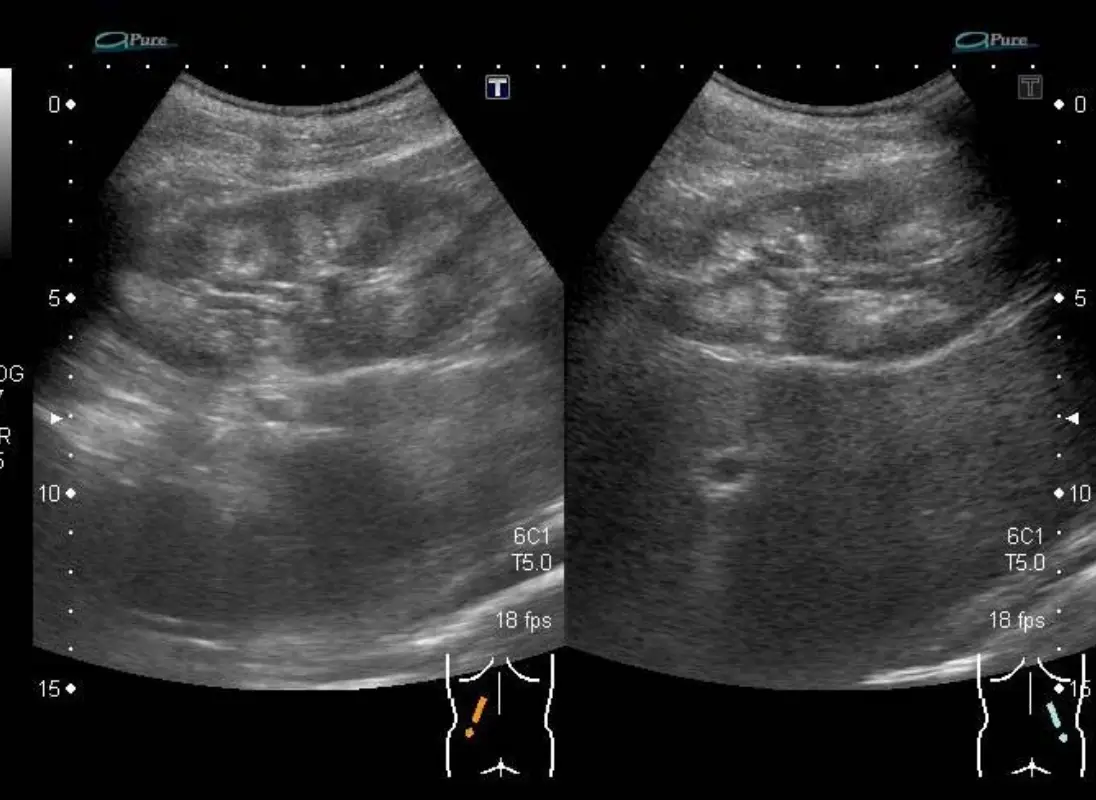

腎臟超音波顯示雙側腎臟的橫切面與矢狀切面掃描(使用 6C1 探頭,T5.0 設定,18fps)。兩側腎臟大小正常,腎臟皮質回音均勻,腎錐體(renal pyramids)無異常高回音,未見腎鈣化(nephrocalcinosis),亦無腎結石或水腎等異常發現。

此正常腎臟超音波結果在本題的鑑別診斷中極為關鍵:

- Bartter syndrome(尤其 Type I/II/IV):長期高鈣尿症(hypercalciuria)可導致腎鈣化,超音波顯示錐體高回音;但**Type III(classic Bartter)**及部分成人發病型可無腎鈣化

- Gitelman syndrome:幾乎不會出現腎鈣化(低鈣尿症保護腎臟)

- 長期 loop diuretic 濫用:可能有腎鈣化,但初期或劑量不高時超音波可正常